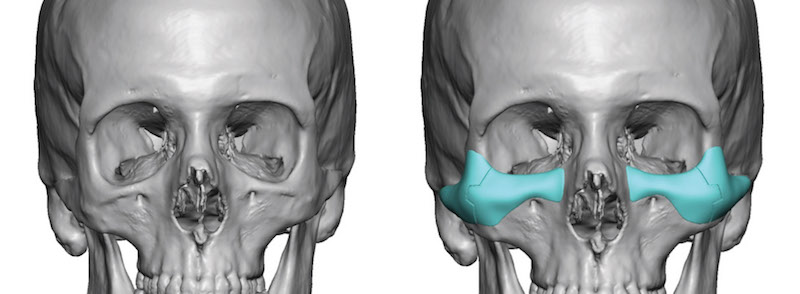

Infraorbital Implants

This procedure enhances the area below the eyes, targeting the infraorbital rim for improved contour and volume.Overview

A small incision is made either inside the lower eyelid (transconjunctival) or just under the lash line (subciliary).A custom or preformed implant is inserted along the infraorbital rim.

The implant is secured with screws or left in place depending on design and surgeon preference.

Pros:

Restores midface volume and reduces hollownessMinimally visible scarring when using internal incisions

Can improve tear trough appearance and support lower eyelid

Cons:

Swelling and bruising for 1–2 weeksRisk of implant shifting that may lead to loss of vision

Possible asymmetry

Requires precise planning for optimal contour and natural results

INFRAORBITAL IMPLANT BEFORE & AFTER

Price: €3,000–€8,000